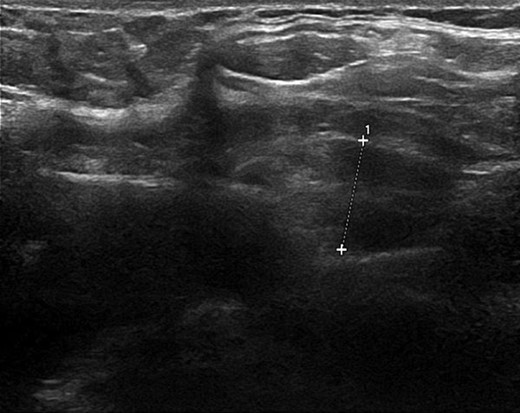

From these results PHPT was suspected and the hypercalcaemia treated with intravenous fluids and a pamidronate infusion. Calcium levels normalized over the next few days along with her psychiatric symptoms suggesting a causative relationship. An ultrasound neck revealed an 11 mm lesion with echogenicity and internal vascularity, likely to be an atypical parathyroid adenoma (Fig. 1). A Sestamibi scintigraphy scan was inconclusive in correlating with the ultrasound or clinical impression, however, evidence was sufficient to warrant surgical exploration with removal of the adenoma as a definitive treatment for the PHPT and psychosis.

Ultrasound neck image illustrating the parathyroid adenoma measuring 11 mm with echogenicity and internal vasculature.

Neck ultrasound is the first line imaging modality and can illustrate abnormal masses. PHPT is caused by adenomas in 85% of cases, hyperplasia in 15% and carcinoma in under 1% of cases [7]. Ultrasound can help to differentiate the cause through assessing location, shape, echogenicity and vascularity.